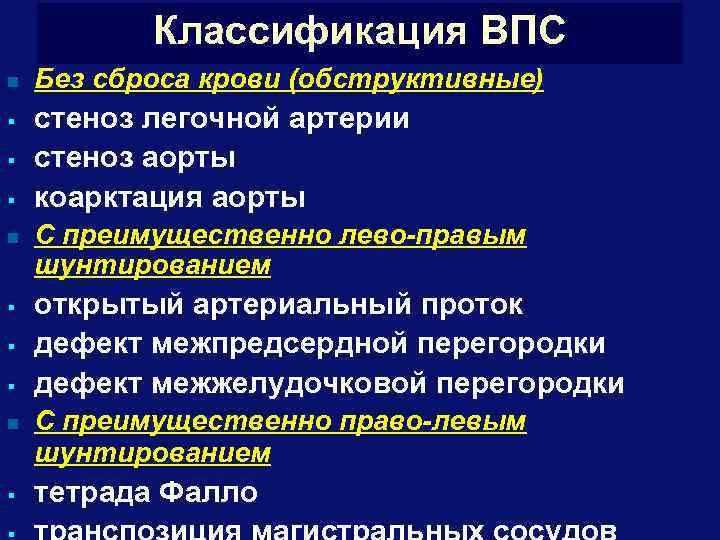

Классификация ВПС n § § § n § Без сброса крови (обструктивные) стеноз легочной артерии стеноз аорты коарктация аорты С преимущественно лево-правым шунтированием открытый артериальный проток дефект межпредсердной перегородки дефект межжелудочковой перегородки С преимущественно право-левым шунтированием тетрада Фалло